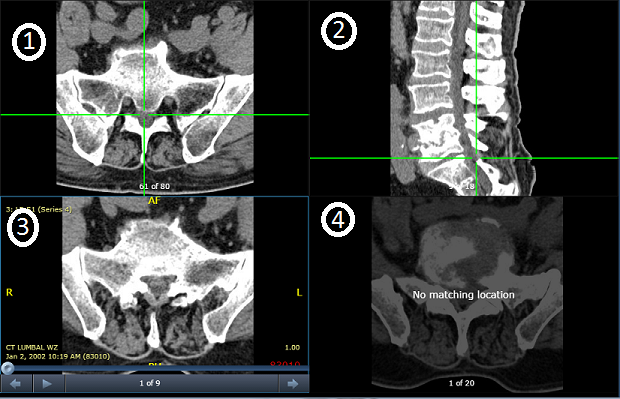

Το παρακάτω παράδειγμα δείχνει το εργαλείο ενεργής σειράς σε διάταξη 2x2 με τέσσερις σειρές.

| 1 | Μια σειρά με αντίστοιχη θέση που εμφανίζεται σε σταυρονήματα |

| 2 | Μια σειρά με αντίστοιχη θέση που εμφανίζεται σε σταυρονήματα |

| 3 | Η σειρά όπου χρησιμοποιείται το εργαλείο ενεργού στόχου |

| 4 | Μια σειρά χωρίς αντίστοιχη θέση |